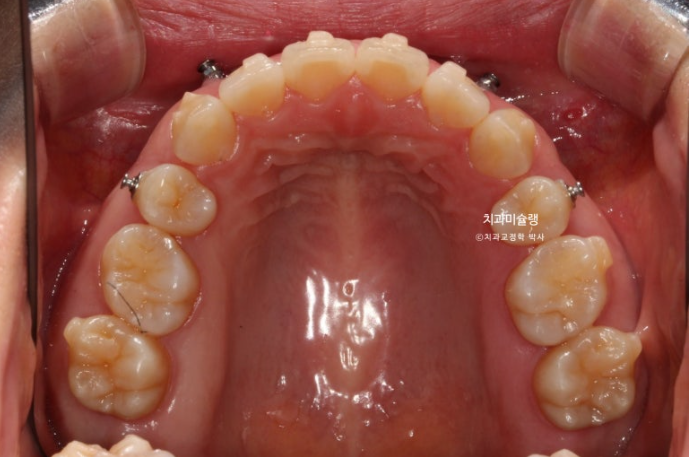

2022.11

돌출입 교정을 위해 멀리 지방에서 오신 환자분입니다.

윗니 돌출이 심합니다.

아랫니 기준으로 약 1센치가 더 튀어나와 있습니다.

위 아래 앞니 간격은 1-2mm 가 정상입니다.

아래 치열은 덧니가 심한 상황입니다.

골격분석 결과 심한 상악골 전방 돌출을 동반한 골격성 2급 부정교합 입니다.

상악골 과잉에 의한 돌출은 돌출입 교정 중에서도 난이도가 높습니다.

상악과 하악의 골격 부조화가 심해 아래턱이 상대적으로 뒤로 밀려있는 상태여서 위 앞니 각도를 이상적으로 유지하기가 쉽지 않습니다.

입이 안 다물어질 정도의 윗니 돌출과 심한 아래 덧니를 해결하려면 작은어금니 4개 발치는 불가피합니다.